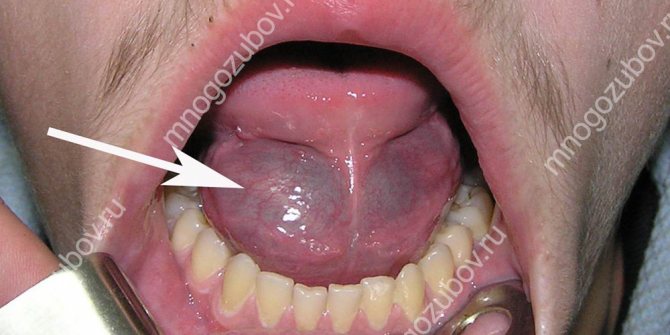

Когда поражена нижняя челюсть, появляется неприятный запах изо рта, отечность, опухает язык. Возникает ощущение, словно болит шея, зуб или десна (в стоматологии нередки случаи, когда пациент обращается за помощью «не по адресу»).

Заболевание получило название «одонтогенная флегмона челюстно-лицевой области» (ЧЛО).

Человеку с таким диагнозом становится сложно говорить и глотать, поскольку отек охватывает окологлоточное пространство.

Могут возникать проблемы с дыханием. Поднимается температура. Лицо становится ассиметричным. Лечение не терпит отлагательств, поскольку велика вероятность потери зубов, тромбоза лицевых вен, асфиксии.